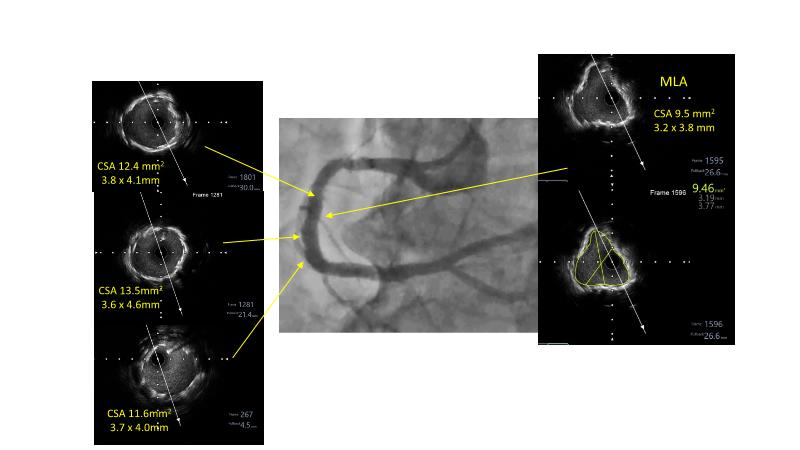

• To understand why the use of IVUS imaging is different from seeing with experienced eyes to achieve improved left main bifurcation outcome